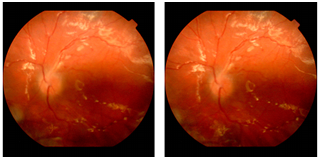

Prognosis of vision in the right eye was nil and explained to the patient. Left eye was managed with phacoemulsification pars plana vitrectomy, endolaser and injection of silicone oil. Intraoperatively, there was inferotemporal dialysis extending from 4.00 to 7.00 o clock position. There was extensive subretinal glial proliferation and preretinal membranes. Peripheral vitrectomy was performed with scleral depression and endolaser was performed. Because of the difficulty of maintaining a facedown position and the possibility of further self-injury, an encircling silicone belt was placed, and the eye was filled with high viscosity silicone oil. Early postoperative phase was uneventful and visual acuity improved to 20/100 with +4.00 Dsph. Patient was advised to take protective polycarbonate glasses and to patch the eye with plastic shield during sleeping. After 4 months patient presented with sudden decrease of vision in the left eye following uncontrollable punching and jabbing in the left eye. On examination, there were small bubbles of silicone oil in the anterior chamber (Figures 5&6). Retina appeared attached (Figures 7&8). Patient underwent membrane peeling with silicone oil removal after psychiatric consultation and modification of medical therapy for TS. At 6 months, the retina remained attached and the visual acuity was 20/100 in the left eye.

Figure 6 Bubbles of silicon oil- 5 months post operation.

Figure 7 Attached retina with silicone oil in situ - 3 month post operative photo.

Figure 8 Attached retina with silicone oil - 6 month post operative photo.